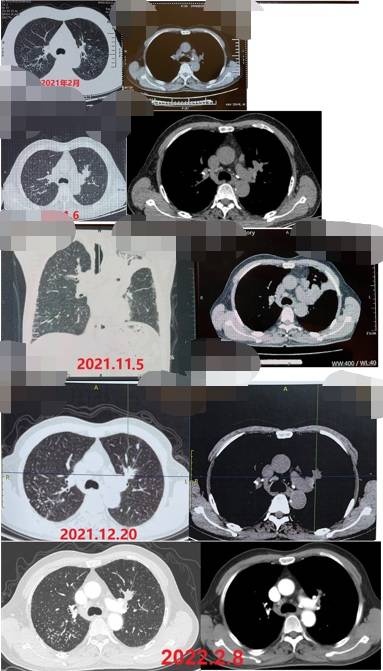

四化前检查

2.8CT医生说小了不少 可是我觉得没怎么小呢 高手帮看看 尺寸是2.1*0.9cm

12.20 二化前CT检查 是小了很多 尺寸是2.1*1.8cm

这次继续K200 白紫300 卡铂400